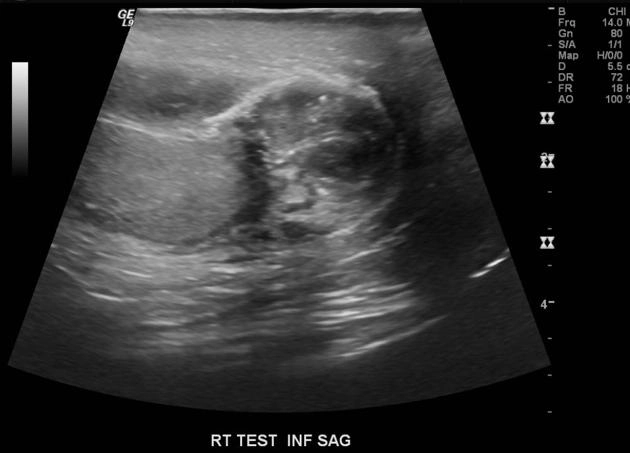

Viêm mào tinh (Epididymitis)